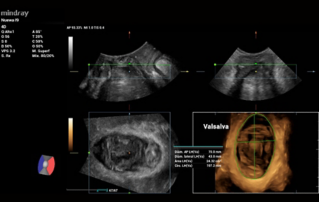

Ultrasound Journal 34 - Use of IOTA-ADNEX & O-RADS risk assessment models in MDT management of Adult Granulosa Cell Tumor

Comprehensive overview of granulosa theca cell tumors of the ovary, covering epidemiology, clinical presentation, diagnosis, treatment options, and prognosis for both adult and juvenile types.